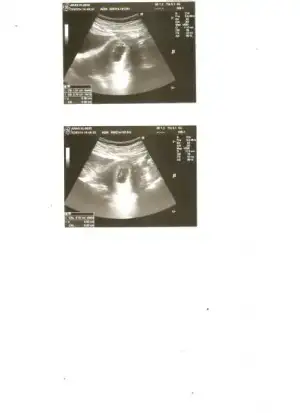

Benimde ikizler kendi arasında bölünerek üçüz oldular. Şuan 7 - 7,5 haftalık üçüde. ve hepsinin kalp atışlarını duyduk. Mucize gibi bir olay nadir rastlanan bir durum dedi. iki kese var biri kendi arasında tekrar bölündü ve tek kesede iki tane bir kesede bir taneler. Riskli ve zor bir gebelik dedi doktor. Rabbim hepimizin yar ve yardımcısı olsun...